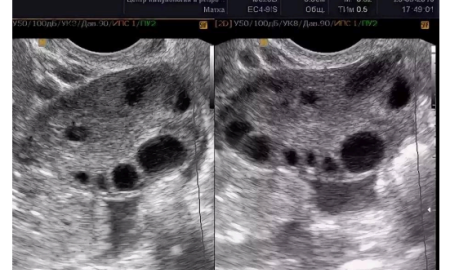

Дополнительную информацию даёт оценка овариального резерва – количества фолликулов в яичниках при УЗИ.

• в возрасте 20–30 лет обычно насчитывается 5–10 и более фолликулов в каждом срезе

• после 35 лет их количество заметно уменьшается

• после 40 лет может оставаться менее трёх фолликулов в срезе. Это говорит о естественном снижении репродуктивного потенциала, но не даёт точного прогноза по срокам менопаузы.

Яичники на УЗИ в 25 лет

Яичники на УЗИ в 40 лет